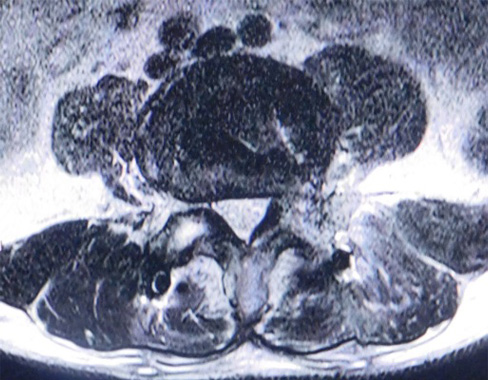

椎間板ヘルニアというと腰椎椎間板ヘルニアが有名ですが、頚椎(くび)のせぼねにも椎間板は存在し、頚椎椎間板ヘルニアを発症することがあります。椎間板組織の一部が飛び出し神経を圧迫する病気です。そのため首から肩、腕、肩甲骨にかけて痛みやしびれが起きます。症状が強い方では力が入りにくくなることもあります。

また、頚椎症性神経根症とは骨棘(こつきょく)とよばれる加齢にともなって生じる骨の変形によって神経の通り道(椎間孔といいます)が狭くなり、神経が圧迫されてしまう病気です。

頚椎椎間板ヘルニアと同様に、首、腕などに痛みやしびれが現れます。

PECF(Percutaneous Endoscopic Cervical Foraminotomyの略称です)は、8~10㎜の小切開で患部にFESSで用いられる専用の内視鏡を挿入し、神経を圧迫の原因となっている骨、靭帯、椎間板を取り除き、椎間孔とよばれる神経が存在する通り道を広げる手術方法です。

傷が小さいため頚椎の周りの筋肉組織などへのダメージがとても少なく、術後の創部の痛みが軽減され、早期の社会復帰を果たすことが可能になります。当院では約1~2週間程度の入院期間で行っております。